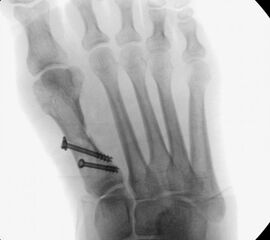

• Gute Stabilität durch Stabilisierung mit einer oder zwei perkutanen Schrauben möglich.

• Kanülierte Schrauben bis 50 mm Länge, 4 mm Durchmesser, Beilagscheiben.

• Akkubohrmaschine, Kirschnerdrähte.

• Röntgenkontrollen (Vorfuß d.p. und seitlich) postoperativ ohne Belastung. Weitere Kontrollen erfolgen 6 Wochen, sowie 3, 6 und 12 Monate jeweils unter Belastung.

• Bruch der medialen Kortikalisbrücke mit Verkürzung und Elevation des 1. Strahles. In diesem Fall muß die Länge des 1.Strahles durch eine quer zur Schaftachse plazierten Schraube gesichert werden. Als Alternative bietet sich eine lange Schraube durch den Schaft als intramedullärer Kraftträger an

• Korrekturverlust durch falsche Platzierung der Osteosynthese.